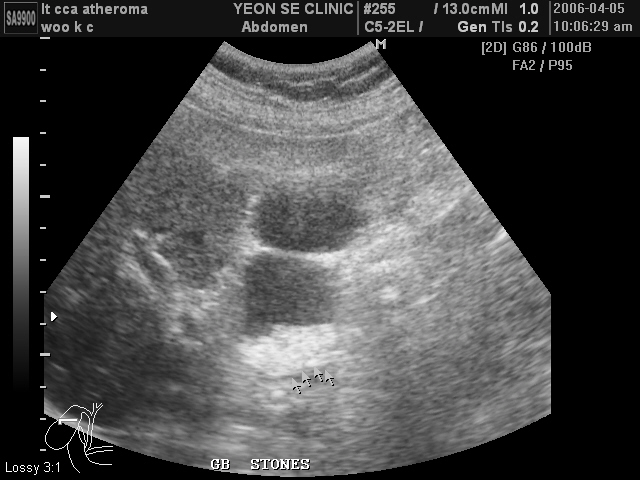

Ultrasonographic data of our patients

Gall stone...